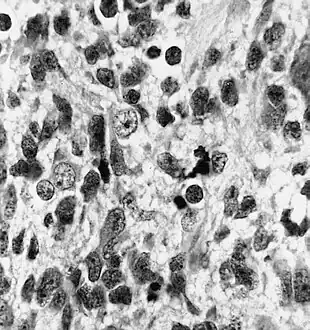

Neuronal differentiation, ranging from neuroblasts to ganglion cells, is seen in some medulloepitheliomas.

Histologically, medulloepithelioma resemble a primitive neural tube and with neuronal, glial and mesenchymal elements.[8][9] Flexner-Wintersteiner rosettes may also be observed.[10]